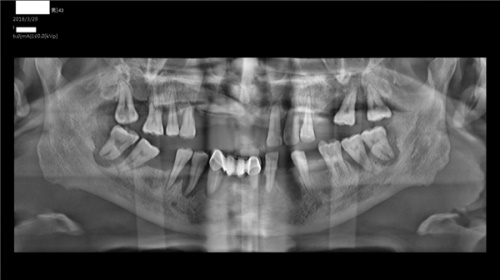

曾有一名42岁的男性顾客,20年前在当地一诊所进行下前牙固定桥修复,备牙过程极为痛苦,因为不好的牙齿治疗体验,让他陷入了疼痛-恐惧-加剧疼痛-更大的恐惧焦虑的恶性循环,便抗拒再去口腔医院,致使20年来未曾进行任何口腔治疗,牙周疾病严重,多颗牙自行脱落。

因为他的孩子在河南大学赛思口腔医院看诊时使用了笑气/氧气镇静,体验很好。尝试使用笑气/氧气镇静,让他迈出了勇敢的一步,在赛思进行口腔检查,接受了11颗问题牙齿的拔除手术,获得舒适化治疗体验,也取得了良好的治疗效果。